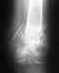

Эндопротезирование коленного сустава

Здравствуйте!Мой папа нуждается в эндопротезировании коленного сустава.Состоит на очереди в УНИИТО.В данный момент состояние очень ухудшилось. Постоянно на обезболивающих уколах, достаточно часто колено стало фиксироваться при этом возникает очень сильная боль.Смотрим статус нашего талона, пишут-госпитализация отложена на следующий год.Можно узнать стоимость данной операции в Институте, нахождение в стационаре,анестезия,эндопротез и то, что необходимо.Пожалуйста, подскажите, что можно сделать в нашей ситуации. Спасибо.